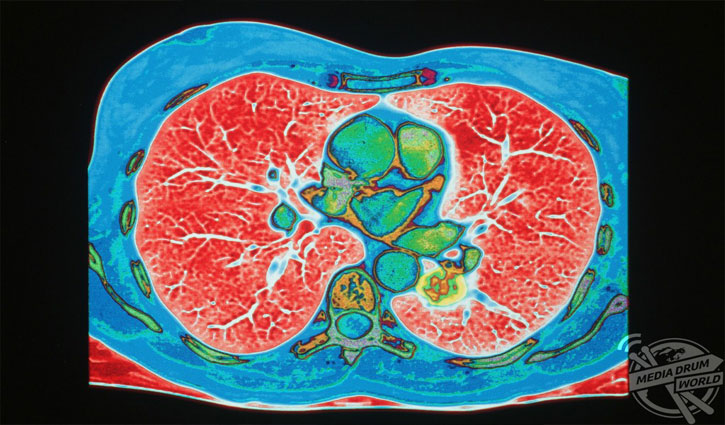

একটি রঙিন সিটি স্ক্যান রিপোর্ট। যা বুকের উপরিভাগে ফুসফুসের টিউমার দেখাচ্ছে (সবুজ রঙে)। প্রতিবছর চার মিলিয়ন মানুষ ফুসফুসের ক্যানসারে মারা যায়। বিশেষজ্ঞরা বলছেন, প্রাথমিক পর্যায়ের খুব কম লক্ষণ দেখা যায়, ক্রমাগত কাশির বা শ্বাসকষ্টের একটা সময় পরে ঘটতে পারে। এই কারণে ক্ষতিগ্রস্তদের আয়ু কম হয়।